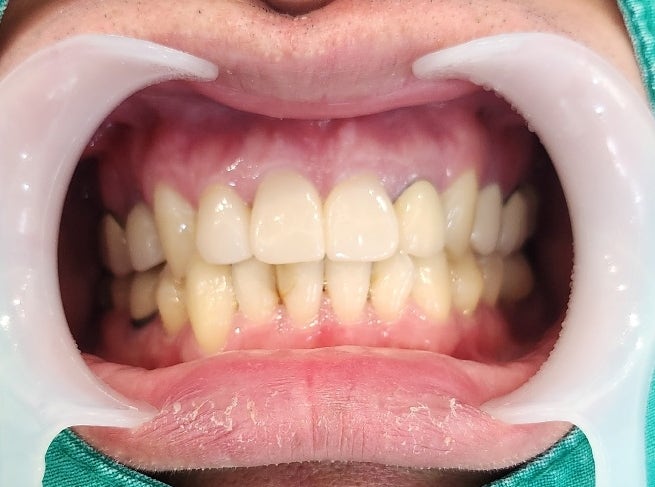

최종 보철물의 형태와 색상

최종 앞니 심미보철 부착 후 사진입니다.

새로운 보철만 바꿨을 뿐인데

기존 치아들까지 부드러운 느낌을 주는 것 같습니다.

주변 치아의 색상을 고려하고

과거의 보철물은 잇몸과의 경계 부위가 자연스럽지 못하고

형태가 투박해 보였습니다.

그 점을 고려하여 치아의 형태를 자연스럽게 제작하려고 노력했습니다.

이번에 치료한 치아 옆의 과거의 보철물도 같이 교체를 했다면

훨씬 자연스러웠을 텐데

일단 큰 불편감 먼저 해소하고 나중에 고민하기로 했습니다.

문제가 생긴 2개의치아는 신경치료

나머지 1개의 치아는 보강 후신경치료 없이 앞니 보철치료를 마무리했습니다.

앞으로는 염증으로 인해 뼈가 소실된 부위가

회복되는지를 지켜보아야 합니다.